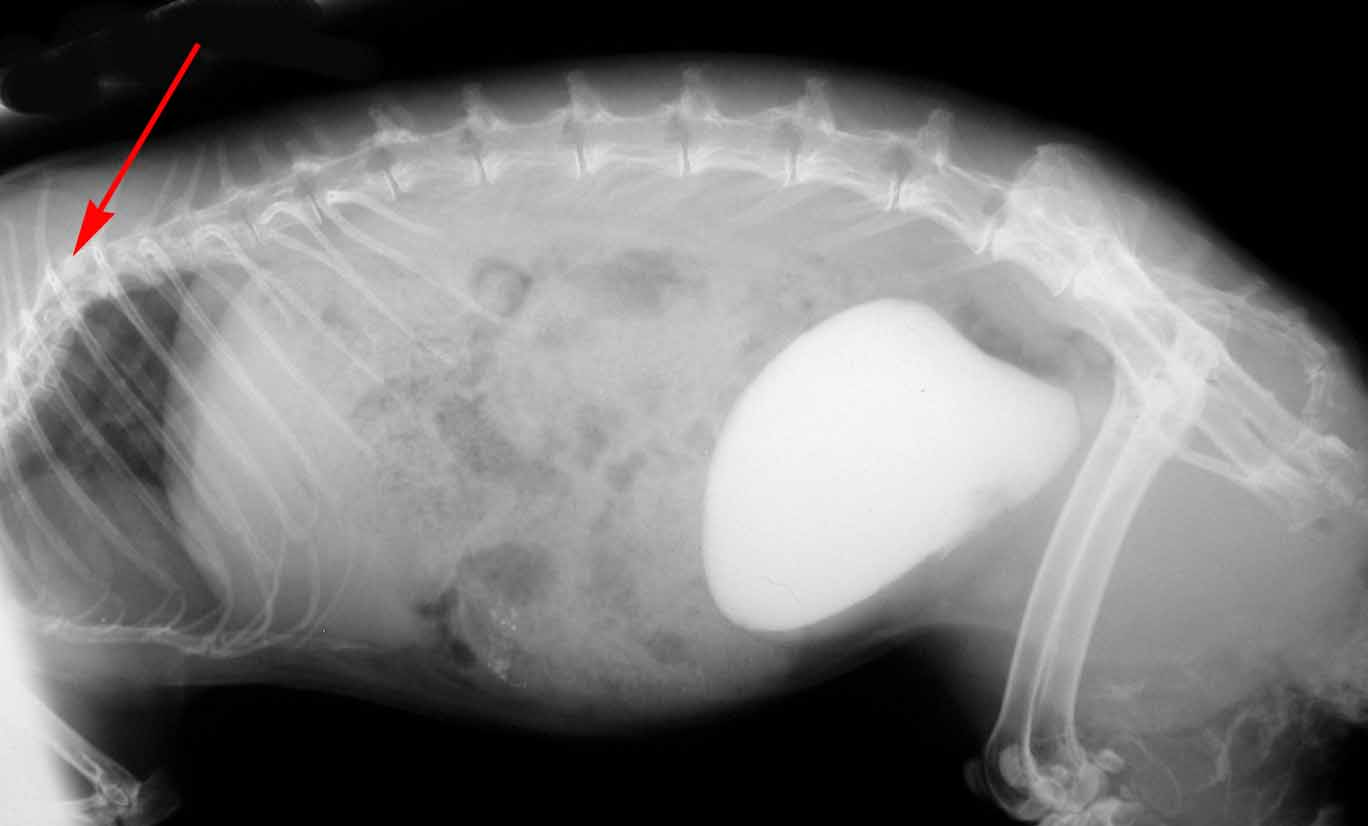

This rabbit has a bladder full of sludge (dense white area) but there is also a deformity in its spinal column that is affecting its ability to urinate properly.